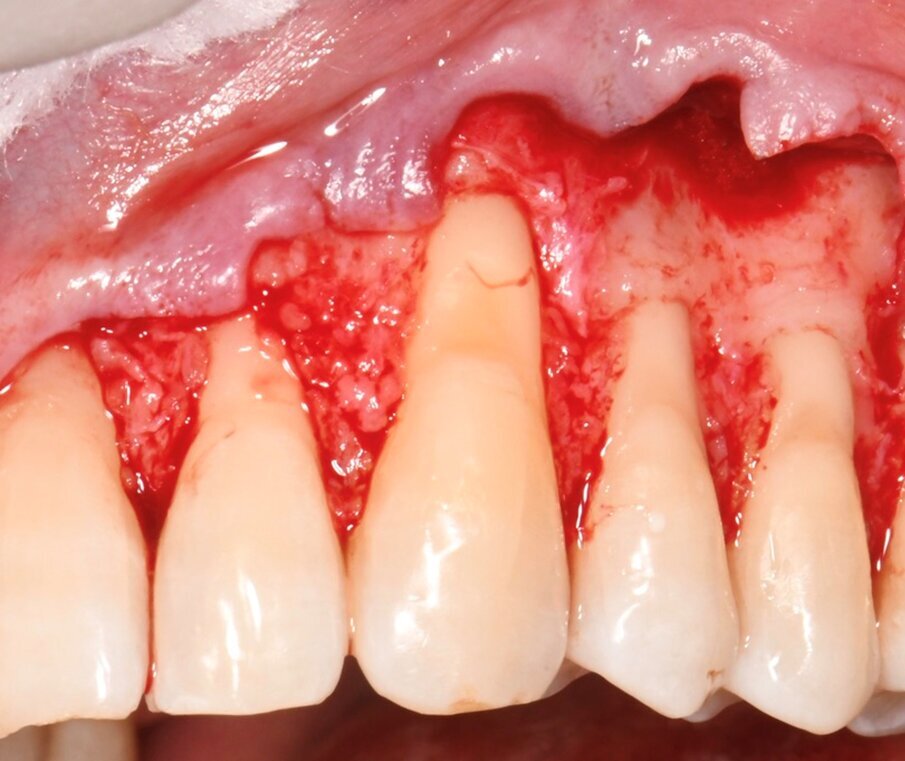

Il caso riguardava un paziente maschio di 38 anni, non fumatore, non affetto da parodontite, che si presentava nello studio per la risoluzione di una recessione gengivale a carico dell’elemento 23, trattato precedentemente con materiale composito (Fig. 1). L’esame clinico evidenziava recessioni multiple nei 4 quadranti associate a lesioni cervicali non cariose (NCCLs). In particolare, erano presenti recessioni gengivali di tipo I a carico degli elementi 21-25 (Fig. 2). Le gengive erano caratterizzate da un fenotipo sottile. Previo trattamento conservativo delle NCCLs eseguito nella settimana precedente a quella dell’intervento, veniva ripristinata la sede della giunzione smalto-cemento in sede 21-25. In accordo con il paziente si conveniva di trattare le recessioni gengivali di tipo I degli elementi 23-25 con una procedura di chirurgia mucogengivale che combinava la tecnica del lembo a posizionamento coronale MCAF e l’innesto di una matrice collagenica tridimensionale di origine equina (XC COLLAGEN Xenomatrix, Bioteck Spa). La sede delle recessioni presentava una sufficiente banda di gengiva aderente (2 mm) che consentiva l’impiego della matrice collagenica. L’area di intervento veniva anestetizzata utilizzando articaina cloridrato 40 mg + 10 µg/ml di adrenalina (Citocartin, Molteni Dental s.r.l). L’intervento per la copertura radicolare veniva eseguito con tecnica MCAF individuando il canino come centro di rotazione del lembo (Fig. 3).

Fig. 3 - Dettaglio delle incisioni primarie, realizzate per definire i limiti coronali del lembo e stabilire il canino come centro di rotazione.

Fig. 4 - Dettaglio del lembo a busta ottenuto mediante scollamento dai piani sottostanti con tecnica a spessore misto (parziale -totale-parziale).